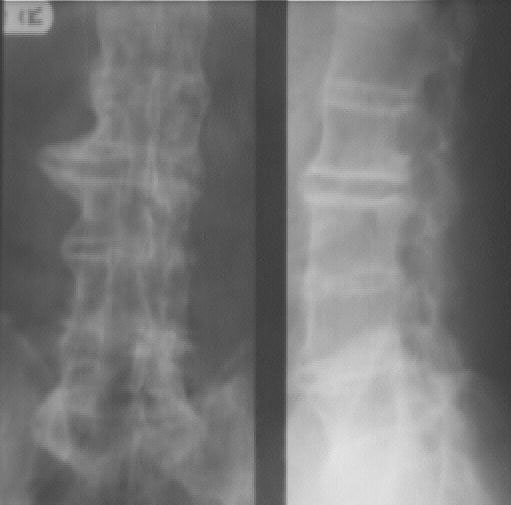

This image shows narrowing of the spaces between the lumbar vertebrae. There is also ankylosis of the facet joints.